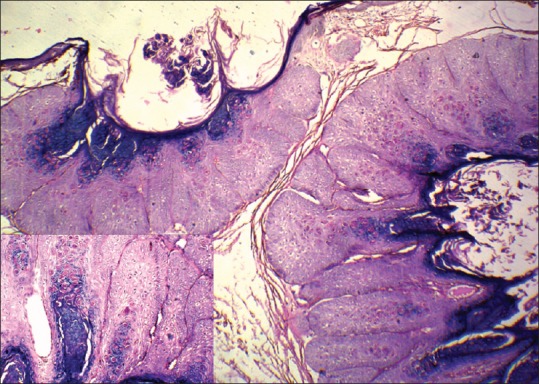

The biopsy was done and histopathology picture is as below [Figure 3] showing hyperplastic epidermis with cells showing intracytoplasmic inclusions.

Figure 3.

Histopathology picture showing lobules of keratinocytes with epidermal hyperplasia and large eosinophilic intracytoplasmic inclusion bodies (H and E, original magnification ×20). Inset shows close up of inclusion bodies (H and E, original magnification ×100)